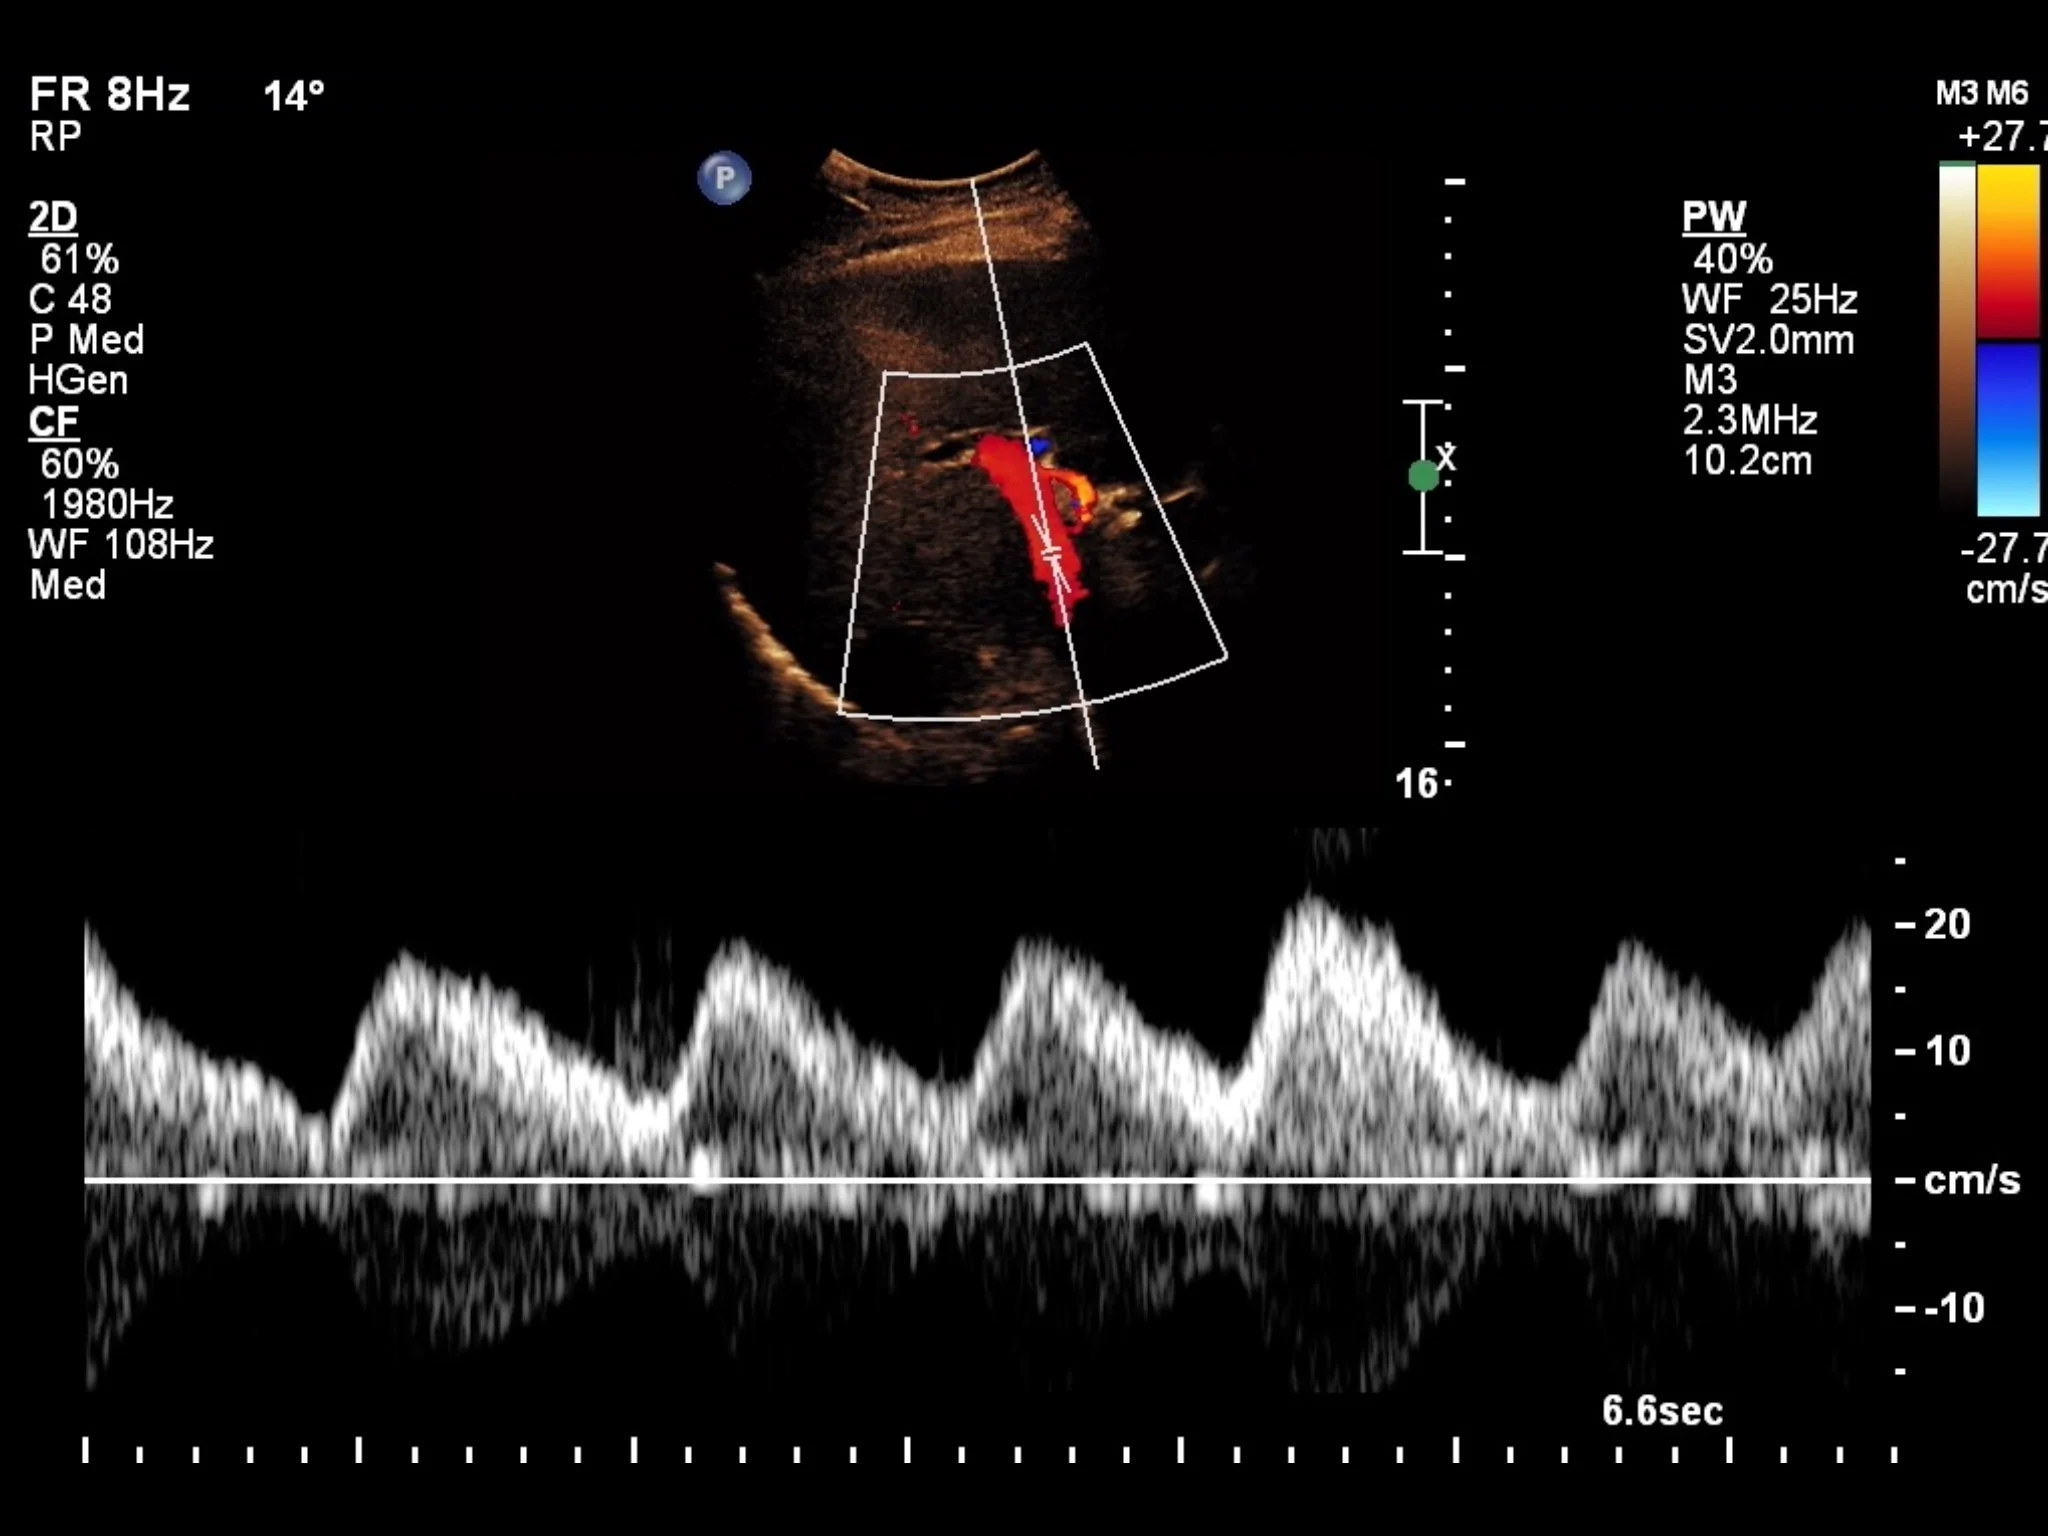

Liver Doppler Ultrasound Pulsatility in Portal Vein Flow — swissnephro

Liver Doppler Ultrasound Pulsatility in Portal Vein Flow — swissnephro Flow Direction Ultrasound How to determine the direction of flow. It’s a painless, noninvasive test of. The direction of the blood flow registered via doppler flow scanning may differ with considering the place of the medical. The frequency spectrum shows blood flow relative to the transducer. Doppler ultrasound provides information about the speed and direction of blood flow through arteries and veins. Depiction. Flow Direction Ultrasound.

Different hepatic portal vein flow patterns can be observed in... Download Scientific Diagram Flow Direction Ultrasound The frequency spectrum shows blood flow relative to the transducer. Here is a helpful tutorial by bill schroedter, bs, rvt, rphs,. How to determine the direction of flow. The machine can assign different colors depending on the direction of flow, also known as phase shift. Color flow doppler is used frequently in sonography to semiquantitative overall blood flow to a. Flow Direction Ultrasound.